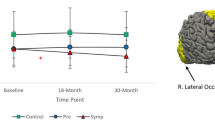

Main effects and Interaction effects on FA

There were no significant interaction effects of Group by Time in any of the regions of interest.

Significant main effects of Group were found in the Precentral region, F (2,72) = 3.20, p = 0.047. However, after correcting for multiple comparisons, this did not remain significant. Controls and pre-HD showed significantly higher FA than symp-HD in this area (see Fig. 1). There were no significant effects of Group in the Rostral Middle or Superior Frontal regions.

There were no significant main effects of Time in any regions of the interest.

Main effects and Interaction effects on AD

There were no significant interaction effects of Group by Time on AD in any of the regions of interest.

Significant main effects of Group were found in the Rostral Middle Frontal region, F (2, 72) = 9.83, p = < 0.01. Controls and pre-HD showed significantly lower AD than symp-HD individuals (see Fig. 2).

There were no significant main effects of Time on AD in any of the regions of interest.

Main effects and interaction effects on RD

There were no significant interaction Group by Time effects in any of the regions of interest.

There were significant main effects of Group in the Precentral, F(2,72) = 3.39, p = < 0.05 and Rostral Middle Frontal Regions, F(2,72) = , p = < 0.01. In the Rostral Middle Frontal region, symp-HD individuals had significantly higher RD than controls and re-HD. In the Superior Frontal region, symp-HD differed significantly from controls, but not from pre-HD. See Fig. 3.

There were no significant main effects of Time in any of the regions of interest.

The primary aim of this study was to examine longitudinal white matter tractography changes in the caudate and precentral, superior frontal and rostral middle frontal brain regions in pre-HD and symp-HD, compared to controls. We did not find a significant interaction effect of Group by Time for any measure in the three regions of interest, nor were there any significant effects of Time. However, we demonstrated significant group differences of FA in the precentral frontal region, AD in the rostral middle frontal region, and RD in the precentral and rostral middle frontal regions with the symp-HD group showing significant differences compared to the pre-HD and control groups (the latter two groups did not differ from one another). Tractography changes were not correlated with change in UHDRS-TMS or DBS in any of the regions of interest.

The finding of significant group level tractography changes in symp-HD from the caudate to the precentral region supports previously established findings that motor circuits are particularly vulnerable in HD (Georgiou-Karistianis & Egan, 2011; Poudel et al., 2014). We found that the symp-HD group had significantly decreased FA, compared to pre-HD and controls, indicating that tracts to the precentral region are likely affected during the symptomatic stage of disease. As HD is primarily a motor disorder, and clinical diagnosis is determined by the development of motor symptoms, it would be expected that white matter connections to the motor cortex would be compromised in symp-HD. Indeed, others have reported similar compromise of the structural connectivity of motor circuits (Georgiou-Karistianis & Egan, 2011; Poudel et al., 2014). In this study, we measured an approximate ~ 4.5% reduction in FA from the caudate to the motor cortex in symp-HD, compared to the FA at baseline, to ~ 2.5% reduction at 30-months. It is unclear why the difference in FA between controls and symp-HD reduced over this time period, but this could be indicative of either selective neurodegeneration or adaptive neuroplasticity (De Erausquin & Alba-Ferrara, 2013; Mole et al., 2016).

Elevated AD was observed in the tracts radiating from the caudate to the rostral middle frontal region in conjunction with significantly increased RD to the precentral and rostral middle regions in symp-HD. These findings were somewhat expected as previous studies had found increased AD and RD in the corpus callosum (Phillips et al., 2013; Rosas et al., 2010) and whole brain (Weaver et al., 2009) in symp-HD, compared to controls (Liu et al., 2016). Whilst an increase in AD can indicate an increased coherence of tracts, this may also be suggestive of a selective neurodegenerative process occurring in symp-HD, which results in fewer neural branches. Alternatively, higher RD may indicate diffusion of water molecules perpendicular to the direction of the tract, potentially reflecting impaired myelin. The rostral middle frontal region houses the dorsolateral prefrontal cortex, which is integral for executive functions including working memory, which is well documented as being impaired in symp-HD compared to controls (Georgiou-Karistianis et al., 2014; Poudel et al. 2015a). Although we did not investigate the relationship between working memory performance and tractography measures in this paper, future studies could utilise this as a measure of functional decline. Together, these findings characterise the potential damage to white matter tracts caused by HD; namely selective neurodegeneration in the rostral middle frontal region accompanied by demyelination of white matter tracts in the precentral and rostral middle frontal regions.